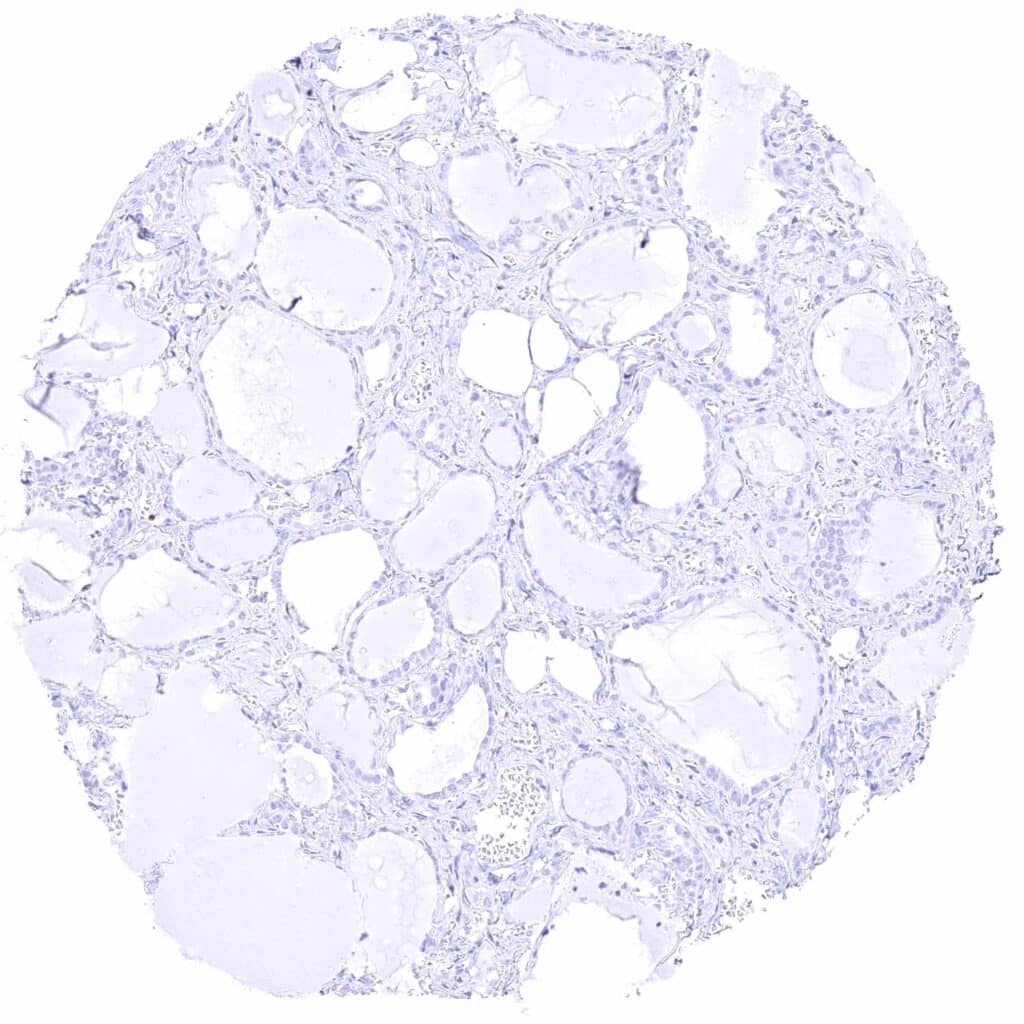

Ovary, follicular cyst